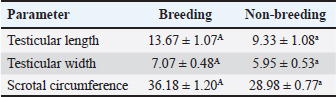

Ultrasonographic examinationIn the rams’ genitalia throughout the clinical evaluation had a uniform consistency, and this investigation did not have any pain reactions. The testicular parenchyma of both ram groups was uniformly echogenic (B-mode) (Fig. 1A), but during the breeding season, the mediastinum testis was large and also more clear compared to out of breeding (Fig. 1B).

Fig. 1. (A) Parenchyma showing uniform echogenicity with large mediastinum tests (length and thickness) and homogenous appearance during the non-breeding season (B), (C) Show large size of epididymis compared to small size during nonbreeding season in(D). (E–H) Show different ecogenicity and variation in the size of male sex gland during breeding and non breeding season. (E) show enlargement and lobulation of seminal gland comparing to loss of lobulation and decrease in its size in (F). (I) also show more clear dorsal part of prostate gland during breeding season. The tail of the epididymis caught on from a slanting plane near the distal pole of the testis. Ultrasonographic scan of the testis showing the tail of the epididymis. The tail appears to be larger, heterogeneous in echotexture, and less echogenic than the testis, which may be related to distension with semen content during the mating season (Fig. 1C). During the non-breeding season, the tail of the epididymis is significantly smaller and more homogenous, indicating decreased sperm storage activity (Fig. 1D; Table 3). Table 3. Comparison of the epididymal tails of rams during and outside the breeding season.

The sex glands of the rats were evaluated ultrasonographically, and the results declared seasonal fluctuations. Higher secretory activity was reflected in the seminal gland by enhanced echogenicity, more lobulated appearance, and clearly defined margins (heterogenous appearance) throughout the breeding season (Fig. 1E; Table 4). Additionally, compared with the nonbreeding phase, the prostate and bulbourethral glands had a denser echotexture and were marginally more noticeable (Fig. 1G–J). The glands seemed smaller, less distinct, and had a more uniform and diminished echogenic pattern during the non-breeding season as a result of lower functional activity (Fig. 1F). Table 4. Seasonal variation in the echogenicity of the glands.